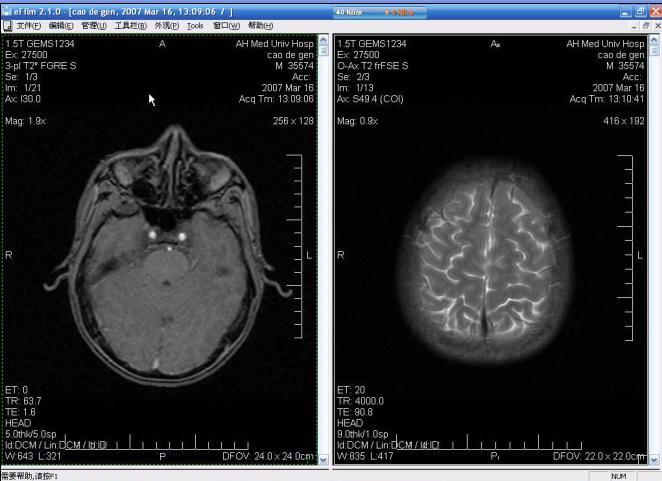

群内有TX推荐efilm 工作站,

efilm 工作站是一个查看和操作医学图像的应用软件。

通过计算机网络使用该软件可对来自多种来源设备(包括CT、MR、US、RF,计算机和特种放射诊断设备,次要捕获装置,扫描仪,图像网关,或者图像来源)的数字图像和数据进行显示、处理、储存以及传输。查看图像时,用户可以自由高速图像的窗宽、窗位;导出Dicom图像到jpg格式、3D及多平面重建图像以及本地打印或Dicom打印图像。